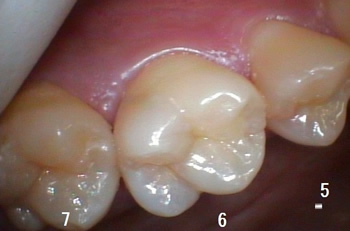

治療の説明をする時に、ここに虫歯があるのですが???と言っても、「どこの事ですか?(本当に穴があいているのですか?)」と思われる事も多く、

特に「歯と歯の間にある虫歯」の説明は苦労する事があります。

治療の前の口腔内診査で撮影した、お口の中の写真で説明しても???の表情、、、

5番目の歯は特に解り難いですが、6番目の歯は「白く」なってますよね!!!

表面的には「虫歯の穴」は確認出来ませんが、説明してレントゲンを撮ります! |